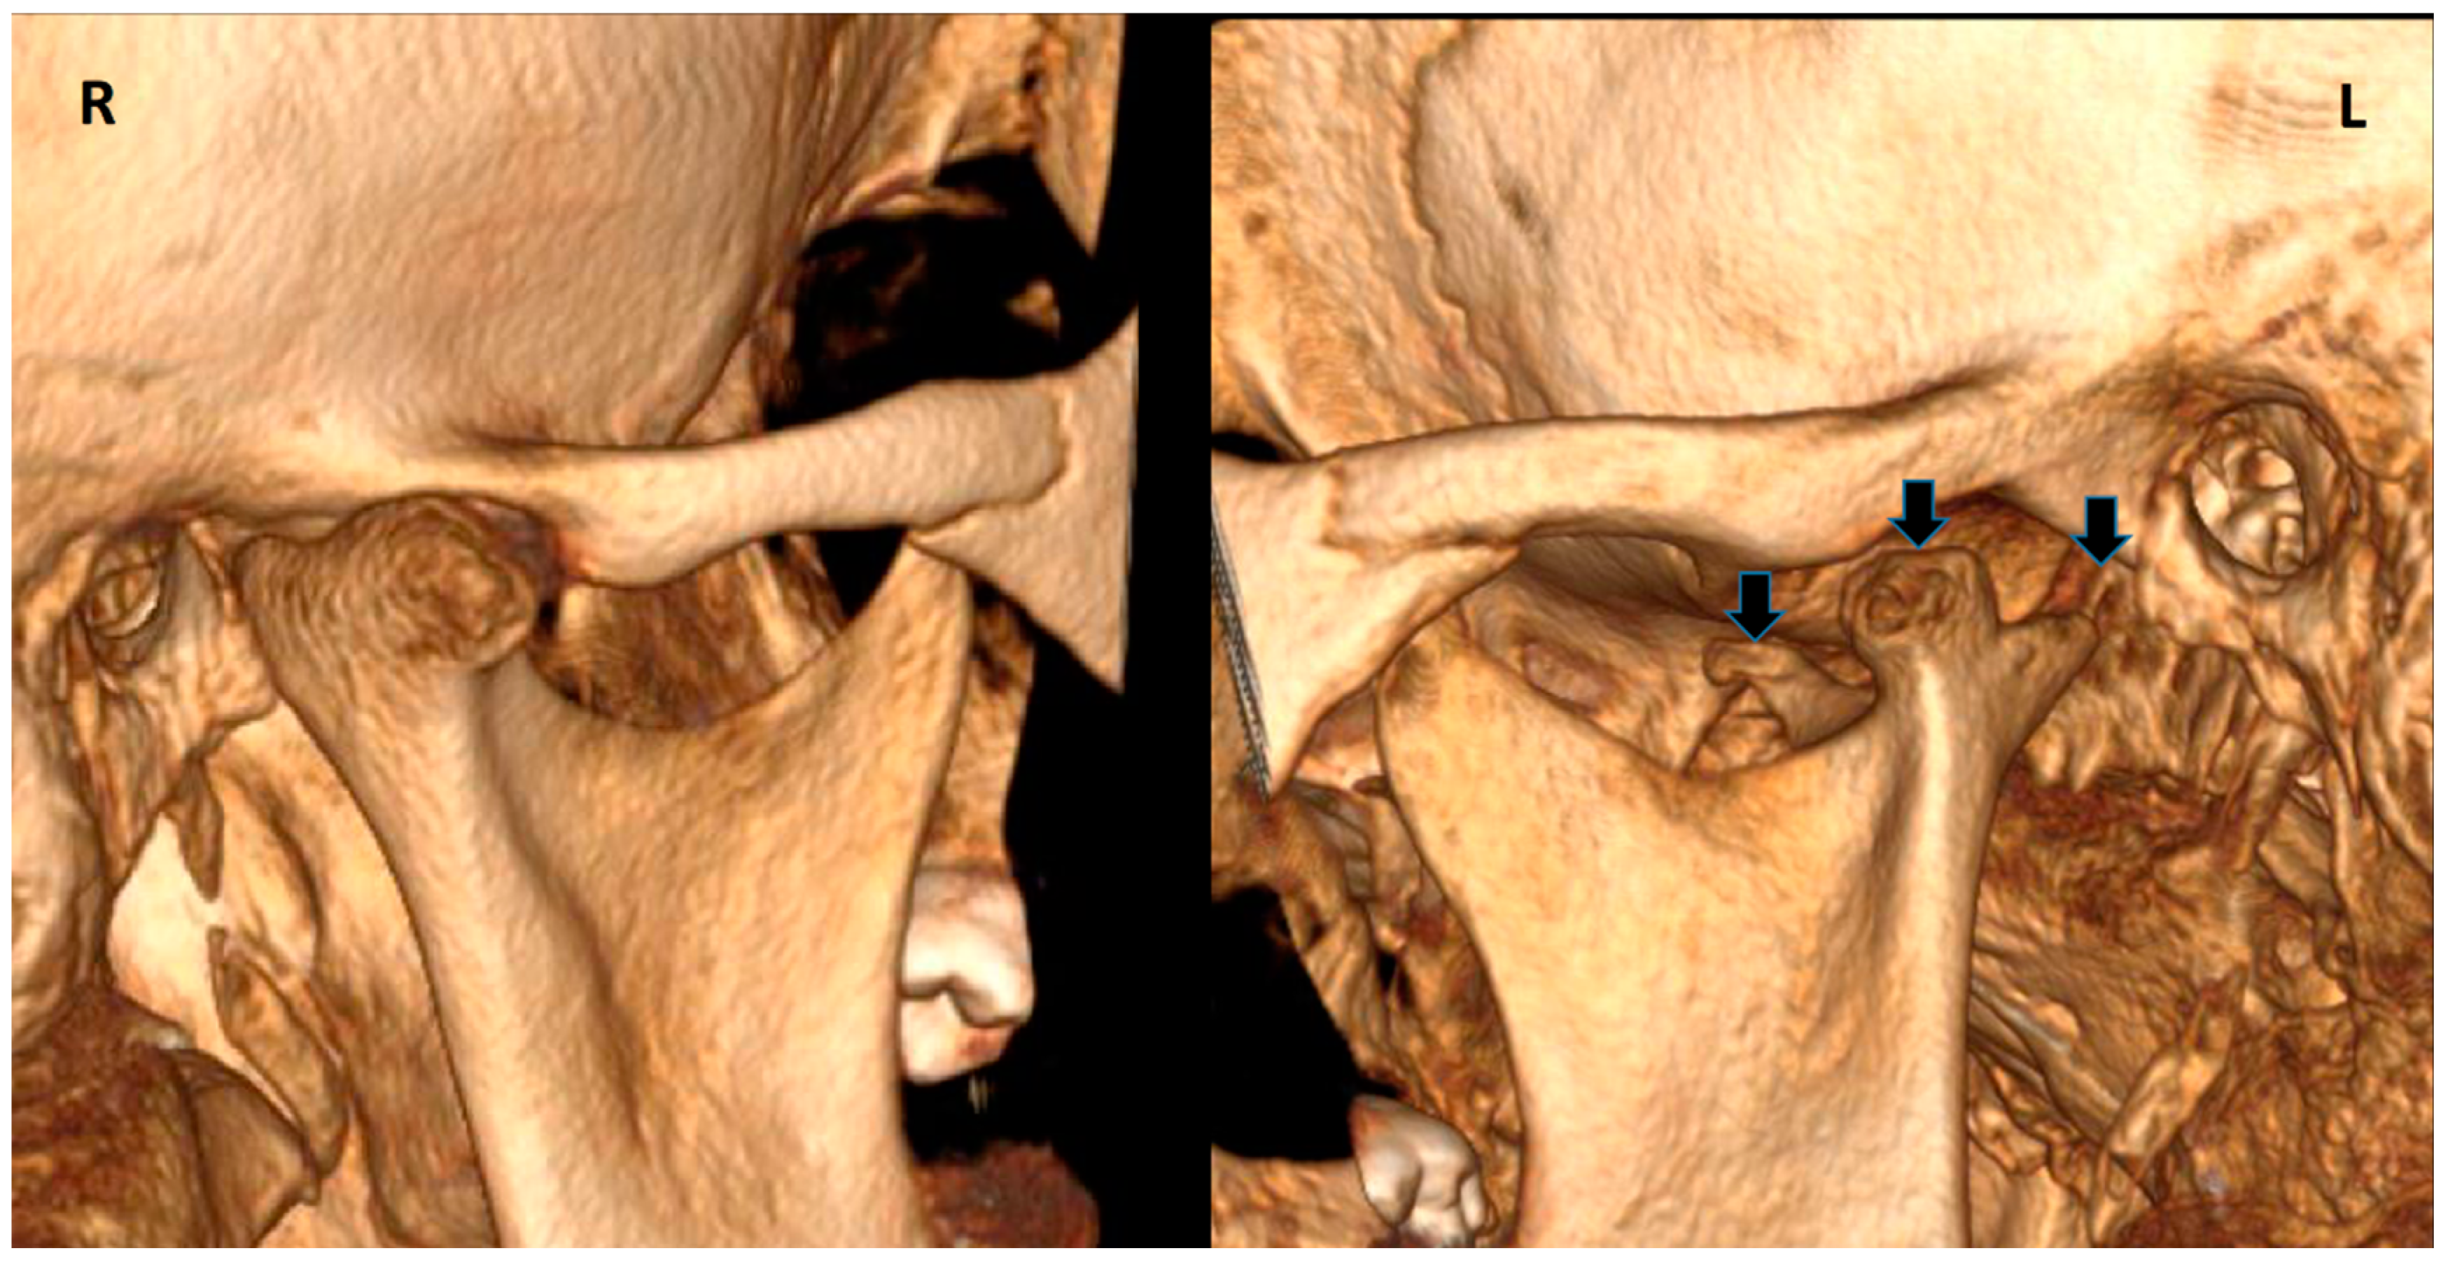

Trifid Mandibular Condyle: Case Report and Current Review of the Literature

2. Case Report

| Prasanna T. et al., 2015 [1] | F, 26 | Mild facial asymmetry, micrognathia & deviation of the mandible to left | - | None | - |

| Hernández-Andara A. et al., 2017 [8] | M, 12 | Facial asymmetry & a clicking noise in the left TMJ | Trauma | FU | - |